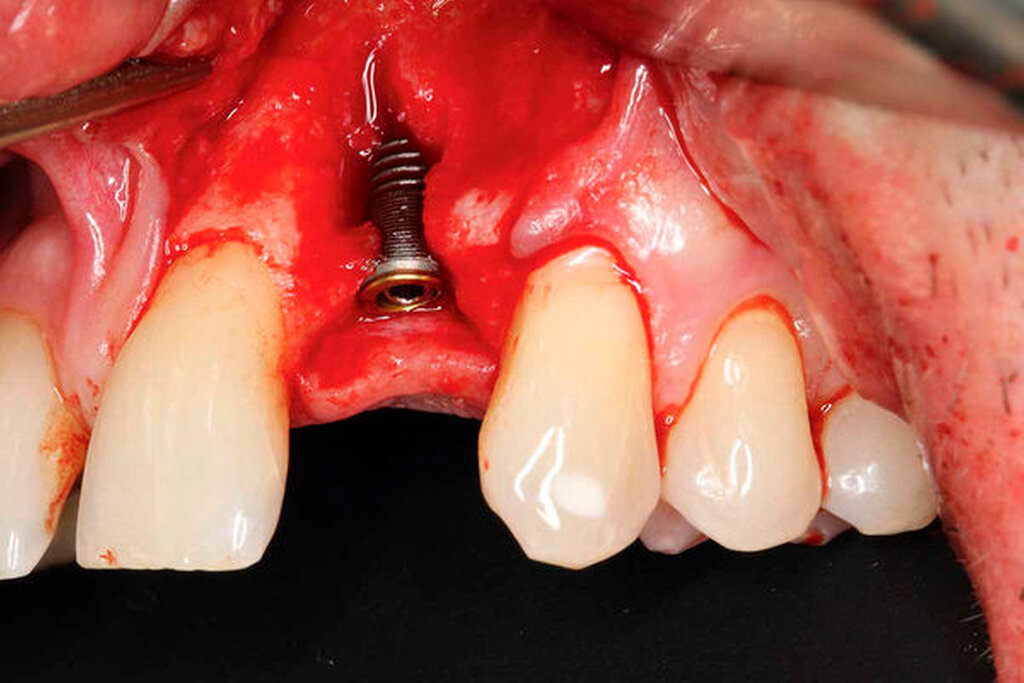

Nach Lappenbildung und Darstellung des Kieferkamms erfolgte die Aufbereitung des Implantatlagers gemäß Protokoll des Implantatherstellers. Anschließend wurde ein Implantat (ASTRA TECH Implant SystemTM EV, Dentsply Sirona, York, USA) inseriert (Abbildungen 3a bis 3c).

Die zuvor gewonnene und aufbereitete Dentinscheibe wurde mit Osteosyntheseschrauben (microscrews, Stoma, Emmingen-Liptingen, Deutschland) lateral des Defekts fixiert und das aufbereitete Dentinpartikulat in den Hohlraum zwischen Zahnscheibe und Implantat eingebracht (Abbildung 3d). Der Wundverschluss erfolgte spannungsfrei mit nichtresorbierbarem Nahtmaterial (Supramid 5/0, Serag-Wiessner, Naila, Deutschland). Postoperativ wurde ein DVT als Röntgenkontrolle angefertigt. Dieses zeigt das Implantat regio 22 in der Sagittalebene. Deutlich erkennbar ist die fixierte Zahnscheibe (Abbildung 4a).